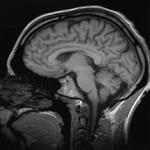

Je suis tombé sur cette image "Gif" ce matin en allant sur la page Wikipédia d'"Imagerie par résonance magnétique".

L'information y était disponible (*), illustrée également de ce "gif".

Je reste toujours complètement bluffé par ces images au delà de leurs fonctions diagnostiques.

Pourtant, ces planches ont pour moi une certaine dimension artistique.